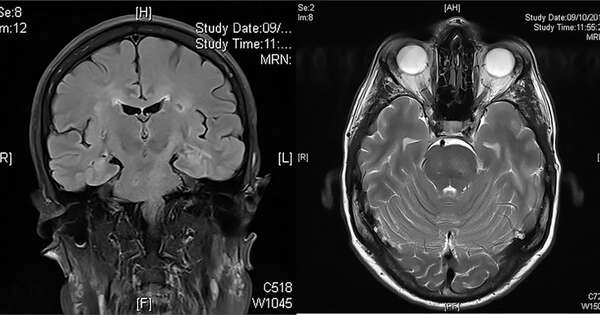

La encefalopatía hipertensiva se caracteriza por cefalea, trastornos visuales y alteraciones del sensorio. Foto: Ilustrativa ...[Leer más]